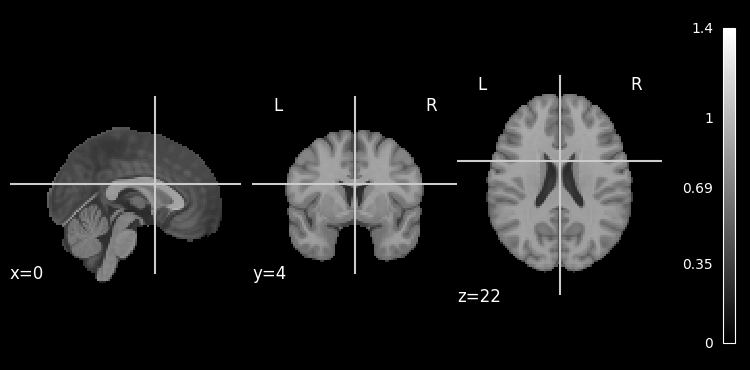

plotting.plot_anat(mni_brain)

<nilearn.plotting.displays._slicers.OrthoSlicer at 0x7f15f950d400>

../../_images/f77ae20518ac0914d60116cde8ee69db48326831d9dfc43a85209638e2f549bc.png